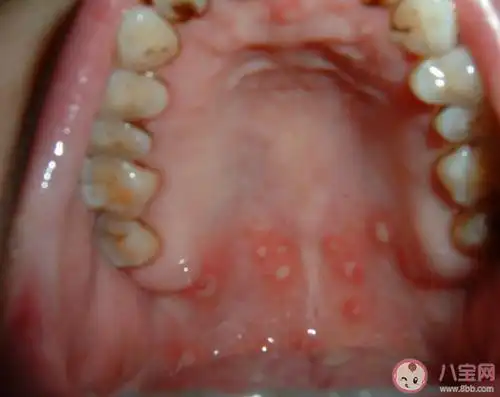

复发性口腔溃疡有办法根治吗多久没愈合要看医生